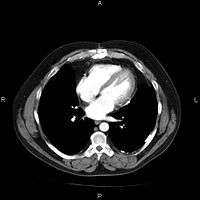

Most PACSs handle images from various medical imaging instruments, including ultrasound (US), magnetic resonance (MR), Nuclear Medicine imaging, positron emission tomography (PET), computed tomography (CT), endoscopy (ES), mammograms (MG), digital radiography (DR), computed radiography (CR), Histopathology, ophthalmology, etc. Additional types of image formats are always being added. Clinical areas beyond radiology; cardiology, oncology, gastroenterology, and even the laboratory are creating medical images that can be incorporated into PACS. (see DICOM Application areas).